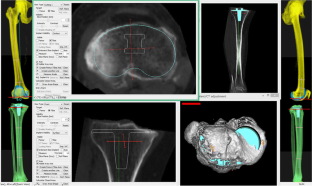

We analyzed preoperative computed tomography images for primary TKA in 106 cases and 157 knees, using three-dimensional planning software. Tibial component position prioritizing maximum coverage of resected bone surface was simulated, and results were compared with the AP axis. Rotational alignment angle was defined as that between a line perpendicular to the tibial AP axis and a line connecting the posterior edge of the tibial component.

Fig. 1